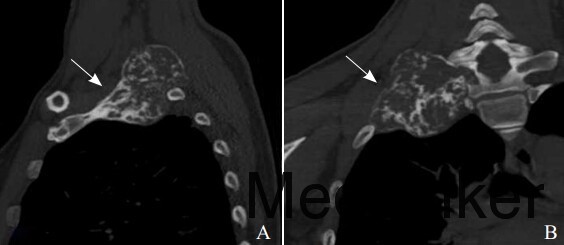

检查:右肩关节CT平扫后行多平面重建:右侧第1肋骨见骨质破坏侵犯T1椎体及横突,病灶呈膨胀性改变,大小约7cm x5cm,密度不均,内见不规则的条片状骨样密度影,骨皮质不连续处可见软组织密度影,周围肌肉软组织及右肺尖呈推压改变。

CT诊断:右侧第1肋骨软骨肉瘤可能性大。 治疗:手术治疗。术中牵开前、中斜角肌后可见一约拳头大小病灶,有完整骨性包膜,向下顶压肺尖,向内连于T1椎体横突,包膜部分破裂后有骨样组织溢出。病理诊断为(肋骨)骨巨细胞瘤。